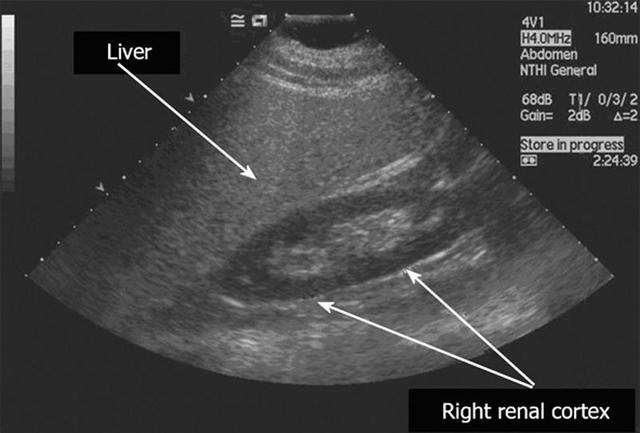

脂肪肝b超影像图

脂肪肝b超,肝右叶钙化灶